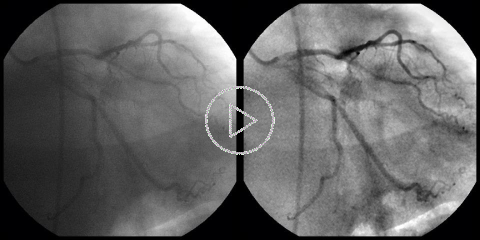

Cardiac DSA:

This is our first attempt to bring Digital Subtraction Angiography (DSA) to cardiology, where the motion of the heart precludes the use of the classic, static DSA. The Coronary DSA solution, presented here, is built around our GPU accelerated algorithms for the elastic image registration. Suppression of the "background" anatomy improves contrast and visibility of the blood vessels, which can be especially important in the case of a heavier patient. Our Cardiac DSA viewer does not require selection of any mask image(s) or pre-detection of blood vessels. Instead, it builds the subtraction mask dynamically, separating the image of the blood vessels from the rest of the anatomy in consecutive frames. |